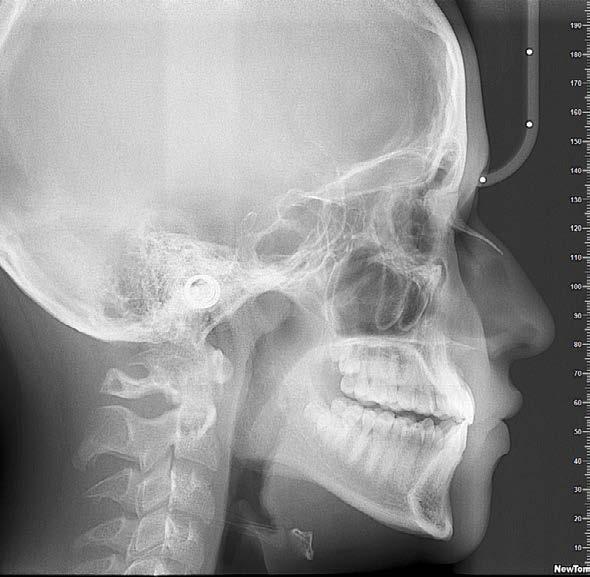

Se presenta un paciente en edad de 15 años y 2 meses. Refiere que acude a consulta por evaluación. En la valoración extraoral presente la hiperdivergencia y sus posiciones dentales (Figura 1), tiene un perfil convexo con hiperactividad del músculo mentoniano e incompetencia labial, y en la radiografía lateral de cráneo inicial (Figura 2) se aprecia el patrón esquelético clase II severo.

En la sobreimposición del componente craneofacial inicio (color negro) y final (color rojo), se observa un paciente con crecimiento, con cambio a nivel de los labios superior e inferior. Con rotación mandibular hacia adelante y hacia arriba, debido a la Lefort I con impactación de 4 mm. El avance mandibular de 9 mm y la mentoplastía de avance de 4 mm (Figura 17).